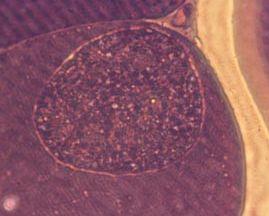

宿主が健康で、感染後に速やかに免疫状態を獲得すれば、多くは原虫の体組織における増殖は抑制され、組織(主として筋肉、脳)にシストを形成してブラディゾイトの状態で存在するようになり、不顕性感染の状態が維持されます。

自然界では多くの感染動物は不顕性感染の状態で維持しますが、宿主が重要な疾病に罹患して抵抗力や免疫状態が低下すると、組織のブラディゾイトは活性化し、タキゾイトとなって増殖しトキソプラズマ症を発症します。